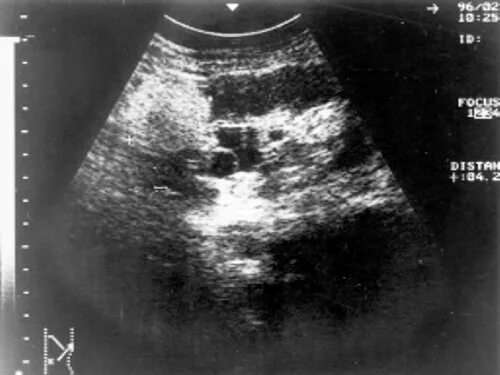

Гиперэхогенное образование в почке что это